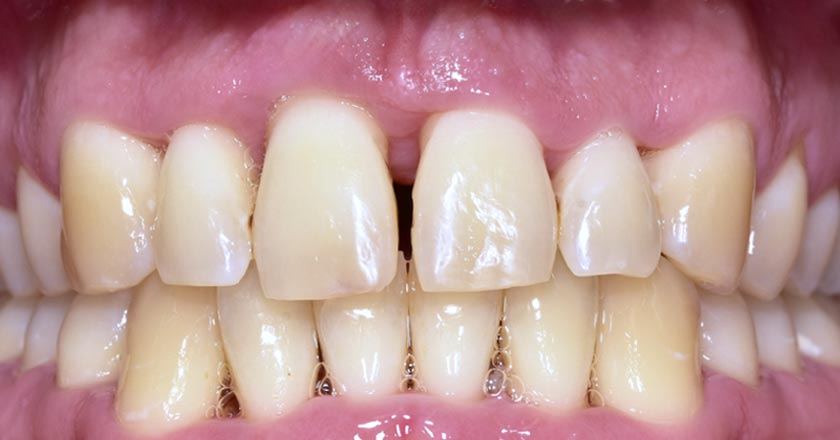

Gum Disease - Before And After